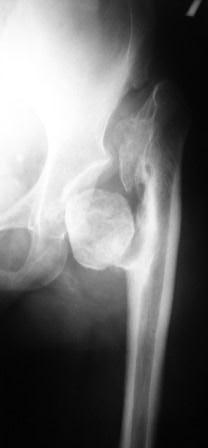

Хотелось бы услышать Ваше мнение по лечению больной 45 лет. Никаких медицинских документов нет. Со слов больной лечили по поводу врожденного вывиха бедра. В 1985г. остеотомия нижней трети бедра и удлинение в аппарате Илизаровна 5см. В настоящее время укорочения конечности нет. Обратилась по поводу выраженного болевого синдрома, который усилился в течение последних двух лет. Судя по рентгенограммам - имел место coxa vara coli lisis с патологическим вывихом бедра. Любое низведение бедра даст грубое удлинение конечности. остеотомии в условиях головки-секвестра мне кажутся бесперспективными.

Где Вы их таких находите? Вариант - эндопротезирование в два этапа: Первый -

чаша с реконструкцией вертлуги и работой на неартрозе выше крыши (убрать его, и слайдинг или даже сегментарная остеотомия вертела или ниже его с низведением и фиксацией). Потянуть бедро вниз аппаратом. Возможно первым этапом бедро не трогать а просто переудлинить. Второй этап - ножка и головка и длина и оставить фиксацию в аппарате? если надо. Четко рассчитать длину

ног - снимки таза всего с нижними конечностями - тогда можно планировать разного типа сечения. Трудности на обоих этапах и риски всякого рода высоки.

Согласен с Вами, что остеотомия бесперспективна.

Мы в подобных случаях отсекаем вертельную область, удаляем промежуточный участок подвертельной области, длиной равной выполненному ранее удлинению и выполняем установку бесцементной ножки.

Для этого хороши новые бесцементные ножки CDH от Biomet, хотя подойдет практически любая бесцементная ножка с дистальной фиксацией.

Важно провести очень тщательное предоперационное планирование и не резецировать больше, чем нужно.